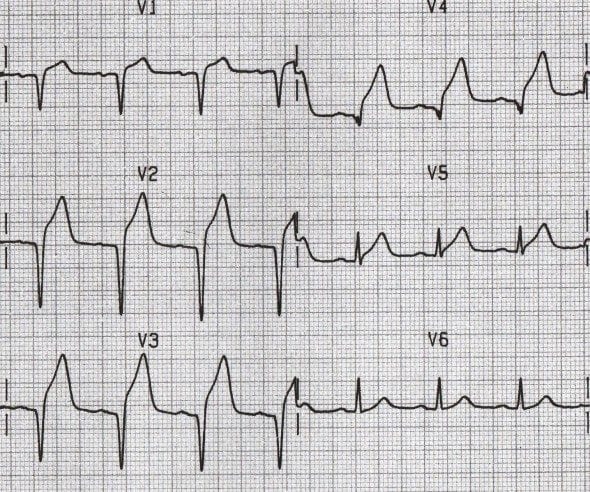

ECG Example – Pathological Q Wave

This ECG demonstrates pathological Q waves in leads V1-V4 (most prominent in V1-V3), due to anterior myocardial infarction.

© Life in the Fast Lane. Licensed under CC BY-NC 4.0